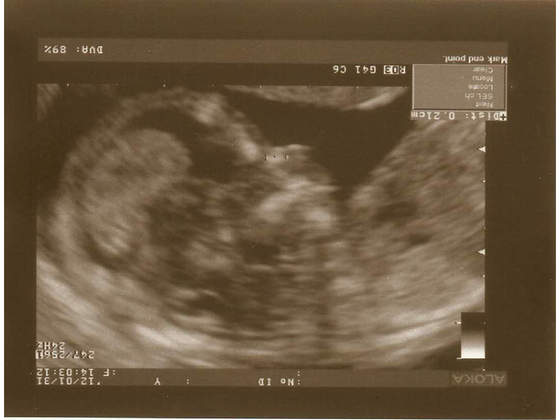

, ale to dopiero 17.02 będzie pierwsze podejście....

Partner będzie mógł być tak czy siak, niezależnie od rodzaju USG.